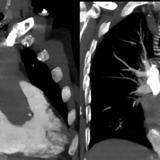

Left atrial enlargement